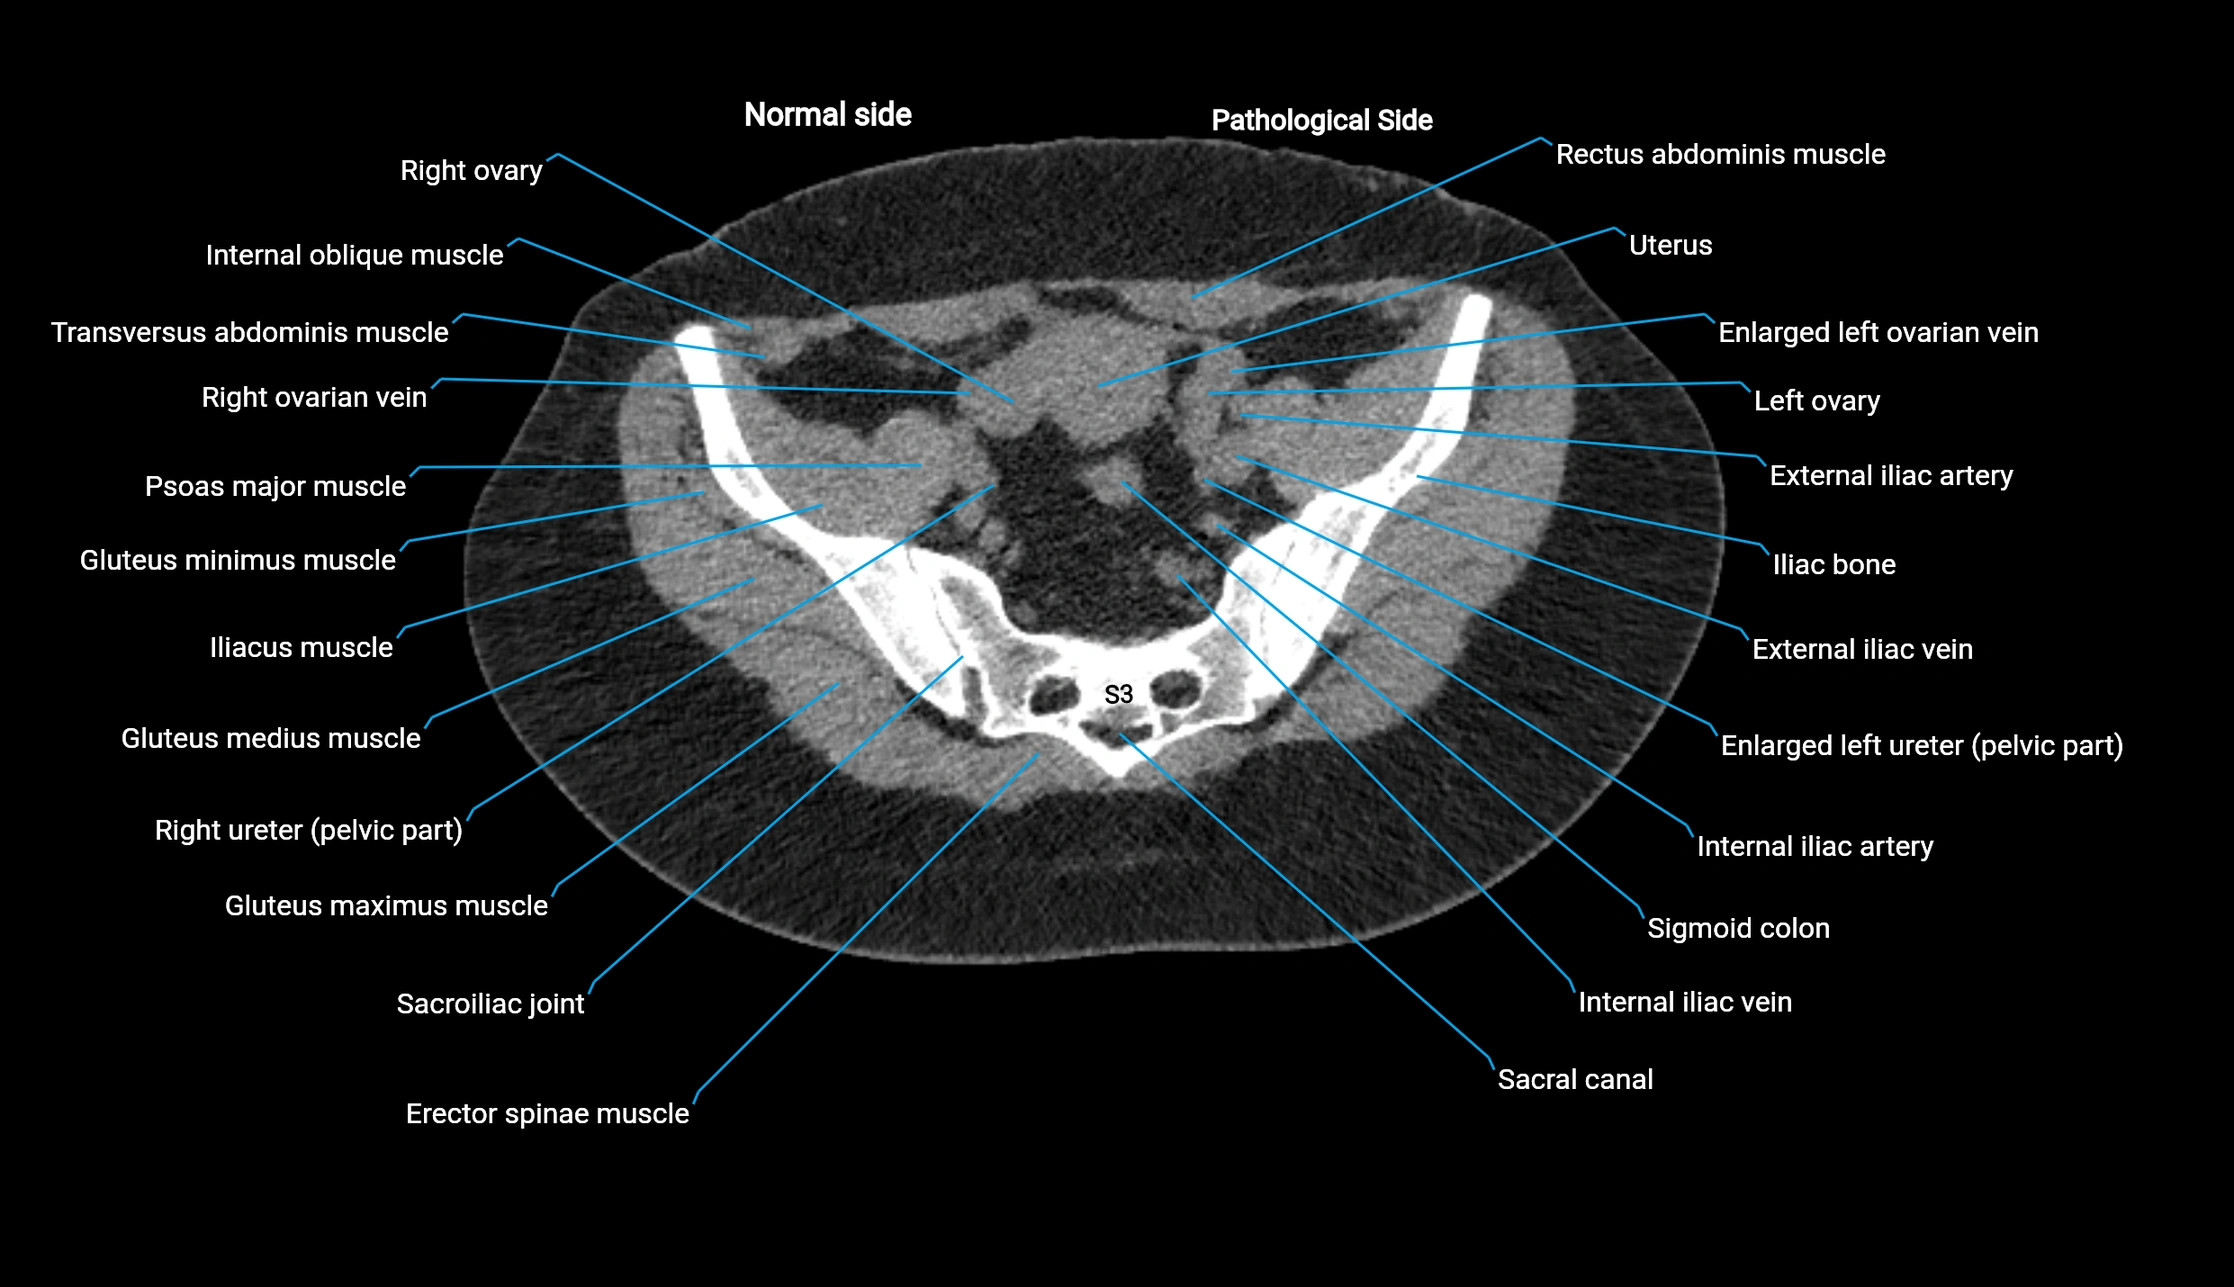

CT Appearance

Non-contrast CT:

• Demonstrates cortical bone of acetabular rim in excellent detail

• Detects fractures, dysplasia, retroversion, or bony overcoverage (pincer impingement)

• 3D reconstructions used in preoperative hip surgery planning